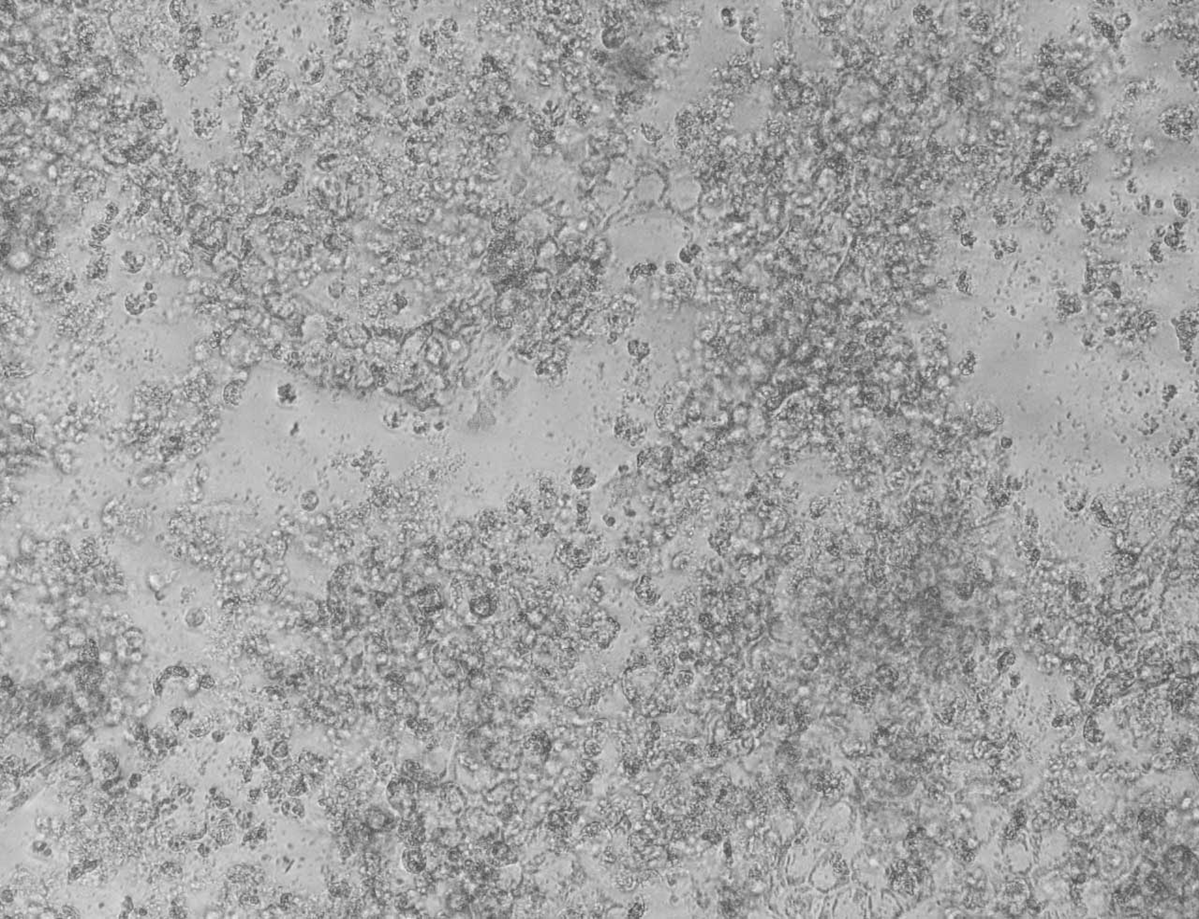

細胞変性効果(CPE)とは?

ウイルスが感染した細胞で起こる形態的な変化のこと。細胞の円形化や膨化、融合、崩壊など、ウイルスによって特徴的な変化がみられ、ウイルスが細胞中で増殖していることを知る重要なサインとなる。

アデノウイルスの中和試験(A549細胞)

A549細胞の剥離や円形化など細胞変性効果(CPE)が多数認められた。

細胞変性効果(CPE)が認められなくなった。つまりアデノウイルス感染が中和された。